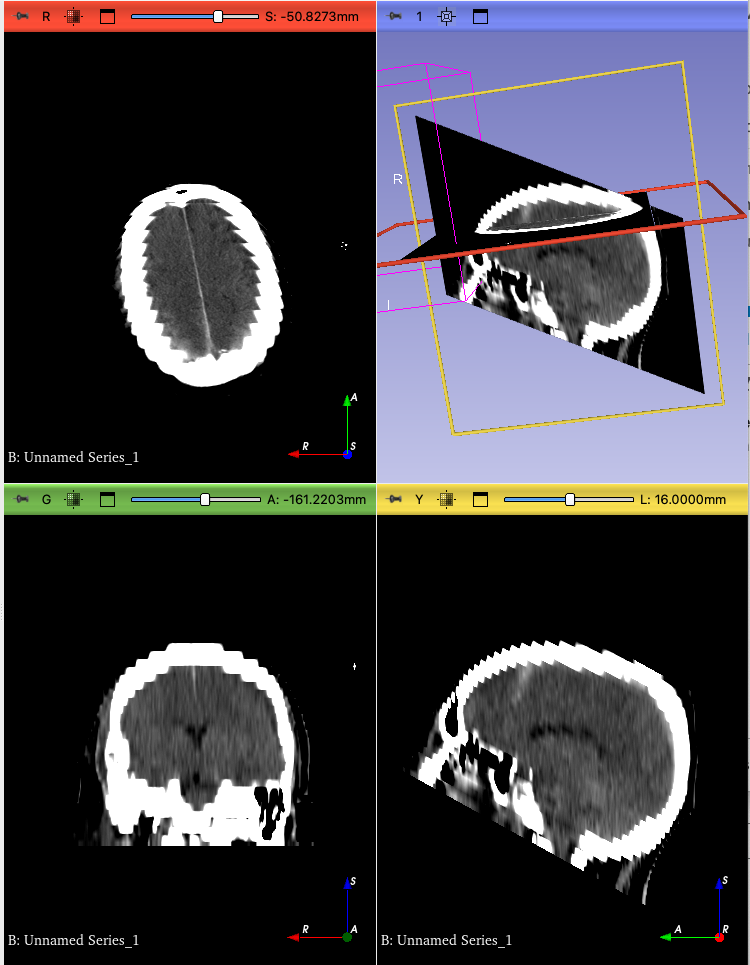

Actual behavior: Plane is listed as ‘Reformat’, scroll tool doesn’t work, and if I drag the slider on the red image, it shows only half the volume, with volume averaging between slices.

It seems that the acquisition normalization does not compensate for cases when the IJK to RAS matrix is linear but non-orthogonal. As a result, a slice view may be set up with non-orthogonal axes, resulting in distorted appearance:

@lassoan as I described above this shearing is only in the reformat view, not in sagittal, so the problem is with the initial Reformat display.